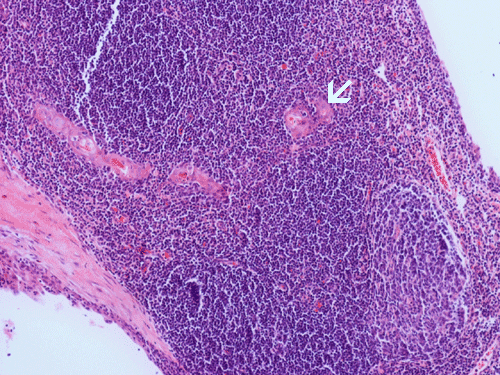

Clinical information: The patient is a 36 year-old woman who presented with a 2 cm swelling in the left side of her neck. The mass was not tender, warm, or painful. The overlying skin was unremarkable. A CT scan was performed and showed a 1.8 x 1.2 cm relatively non-enhancing lesion within the carotid sheath displacing the carotid artery anterioriorly. The clinical and imaging features yielded an empirical diagnosis of an enlarged lymph node. The patient had no history of lymphoma, leukemia, or head and neck tumor. The mass was removed surgically in its entirety and was 2.5 cm in maximum dimension, well encapsulated, located at the level of the carotid bifurcation just lateral to the carotid artery and superiorly extending almost up to the level of the tonsils. The mass did not appear to be in continuity with the jugular vein or the carotid artery. It was not a part of the vagus nerve or sympathetic chain. The followings are representative images.